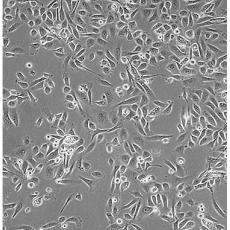

PC-3(PC 3)

中文名稱 人前列腺癌細胞

組織來源 前列腺癌;骨髓轉(zhuǎn)移;男性

形態(tài)特征 epithelial

細胞描述 PC-3源于一位62歲白人男性IV級前列腺腺癌患者的骨轉(zhuǎn)移灶;有低水平的酸性磷酸酶活性和5-α-睪酮還原酶活性。